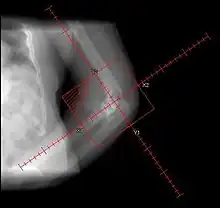

Heterotopic ossification of the elbow, after comminuted fracture and arthroplasty.

Heteropic ossification of the elbow, after comminuted fracture and arthroplasty.

During the early stage, an x-ray will not be helpful because there is no calcium in the matrix. (In an acute episode which is not treated, it will be 3– 4 weeks after onset before the x-ray is positive.) Early laboratory tests are not very helpful. Alkaline phosphatase will be elevated at some point, but initially may be only slightly elevated, rising later to a high value for a short time. Unless weekly tests are done, this peak value may not be detected. It is not useful in patients who have had fractures or spine fusion recently, as they will cause elevations.

The only definitive diagnostic test in the early acute stage is a bone scan, which will show heterotopic ossification 7 – 10 days earlier than an x-ray. The three-phase bone scan may be the most sensitive method of detecting early heterotopic bone formation. However, an abnormality detected in the early phase may not progress to the formation of heterotopic bone. Another finding, often misinterpreted as early heterotopic bone formation, is an increased (early) uptake around the knees or the ankles in a patient with a very recent spinal cord injury. It is not clear exactly what this means, because these patients do not develop heterotopic bone formation. It has been hypothesized that this may be related to the autonomic nervous system and its control over circulation.[3]